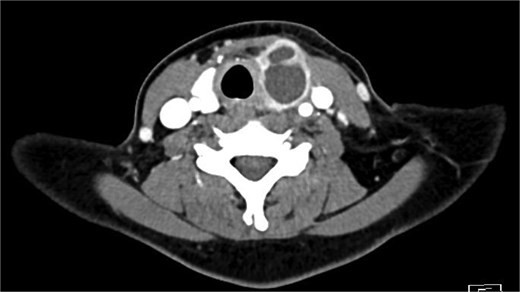

Bloods demonstrated elevated inflammatory markers with a neutrophil count of 7.53 and C-reactive protein of 137. Her biochemistry panel including thyroid function tests were within normal limits. An ultrasound (USS) was performed which showed a cystic/solid nodule in the left thyroid gland that measured 30 × 42 × 22 mm with an estimated volume of 14 ml (Fig. 1). A computed tomography (CT) scan was conducted to ensure no airway compression, it demonstrated the abscess to measure 32 × 26 × 32 mm (Figs 2 and 3). There was no tracheal compression but there was mild inflammatory stranding and hyperenhancement of the nodule consistent with infection.

Axial portal venous phase CT of the neck demonstrating the cystic lesion in the left thyroid gland.